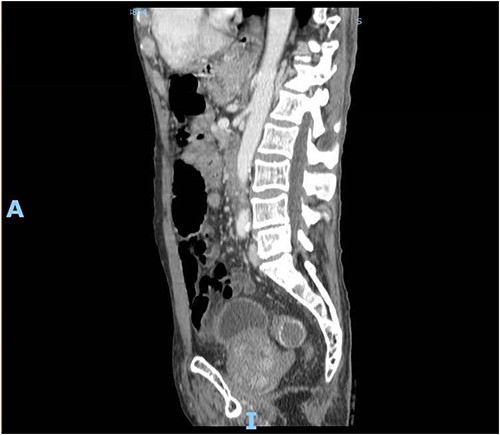

A 89-year-old male patient was admitted to the emergency department complaining of generalized abdominal pain for 4 days. The pain was associated with repeated vomiting and obstipation. He also reported a history of chronic constipation. However, he denied any history of melena, hematochezia, weight loss, night sweats or fever. His past medical history revealed a history of prostatic cancer and pulmonary fibrosis caused by tuberculosis. The patient was diagnosed with symptomatic gallstones two years prior to his presentation, after undergoing an enhanced CT scan of the abdomen (Fig. 1) for abdominal pain. Although he was offered cholecystectomy, he refused the surgery due to his high-risk medical condition.

Enhanced CT scan of the abdomen confirming the presence of a 2.5-cm gallstone.

Upon clinical examination, the patient was vitally stable. Abdominal examination revealed a distended abdomen with generalized tenderness. Digital rectal examination revealed an empty rectum with no palpable masses. Laboratory investigations were unremarkable (Table 1). Abdominal X-ray was done (Fig. 2) and showed dilated large bowel loops suggestive of bowel obstruction. Enhanced CT scan of the abdomen and pelvis was obtained (Figs 3–5) and showed a dilated large bowel loop, with air fluid level. A 2.5-cm gallstone was noted, impacting the sigmoid colon and causing partial large bowel obstruction. There was evidence of pneumobilia with air foci within the gallbladder with a suspected fistula with the hepatic flexure.

Enhanced CT scan of the abdomen showing a gallbladder stone impacted at the sigmoid colon, with a significantly enlarged prostate causing narrowing of the rectosigmoid junction (sagittal view).